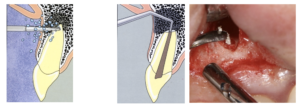

MTA

根尖から感染部を除去 逆根管充填、根尖封鎖